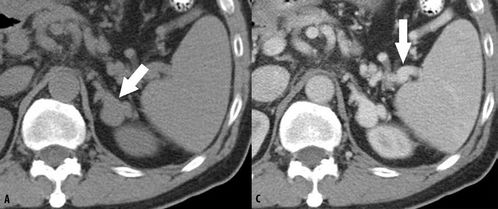

CT的工作程序是這樣的:它根據(jù)人體不同組織對X線的吸收與透過率的不同,應(yīng)用靈敏度極高的儀器對人體進(jìn)行測量,然后將測量所獲取的數(shù)據(jù)輸入電子計(jì)算機(jī),電子計(jì)算機(jī)對數(shù)據(jù)進(jìn)行處理后,就可攝下人體被檢查部位的斷面或立體的圖像,發(fā)現(xiàn)體內(nèi)任何部位的細(xì)小病變。